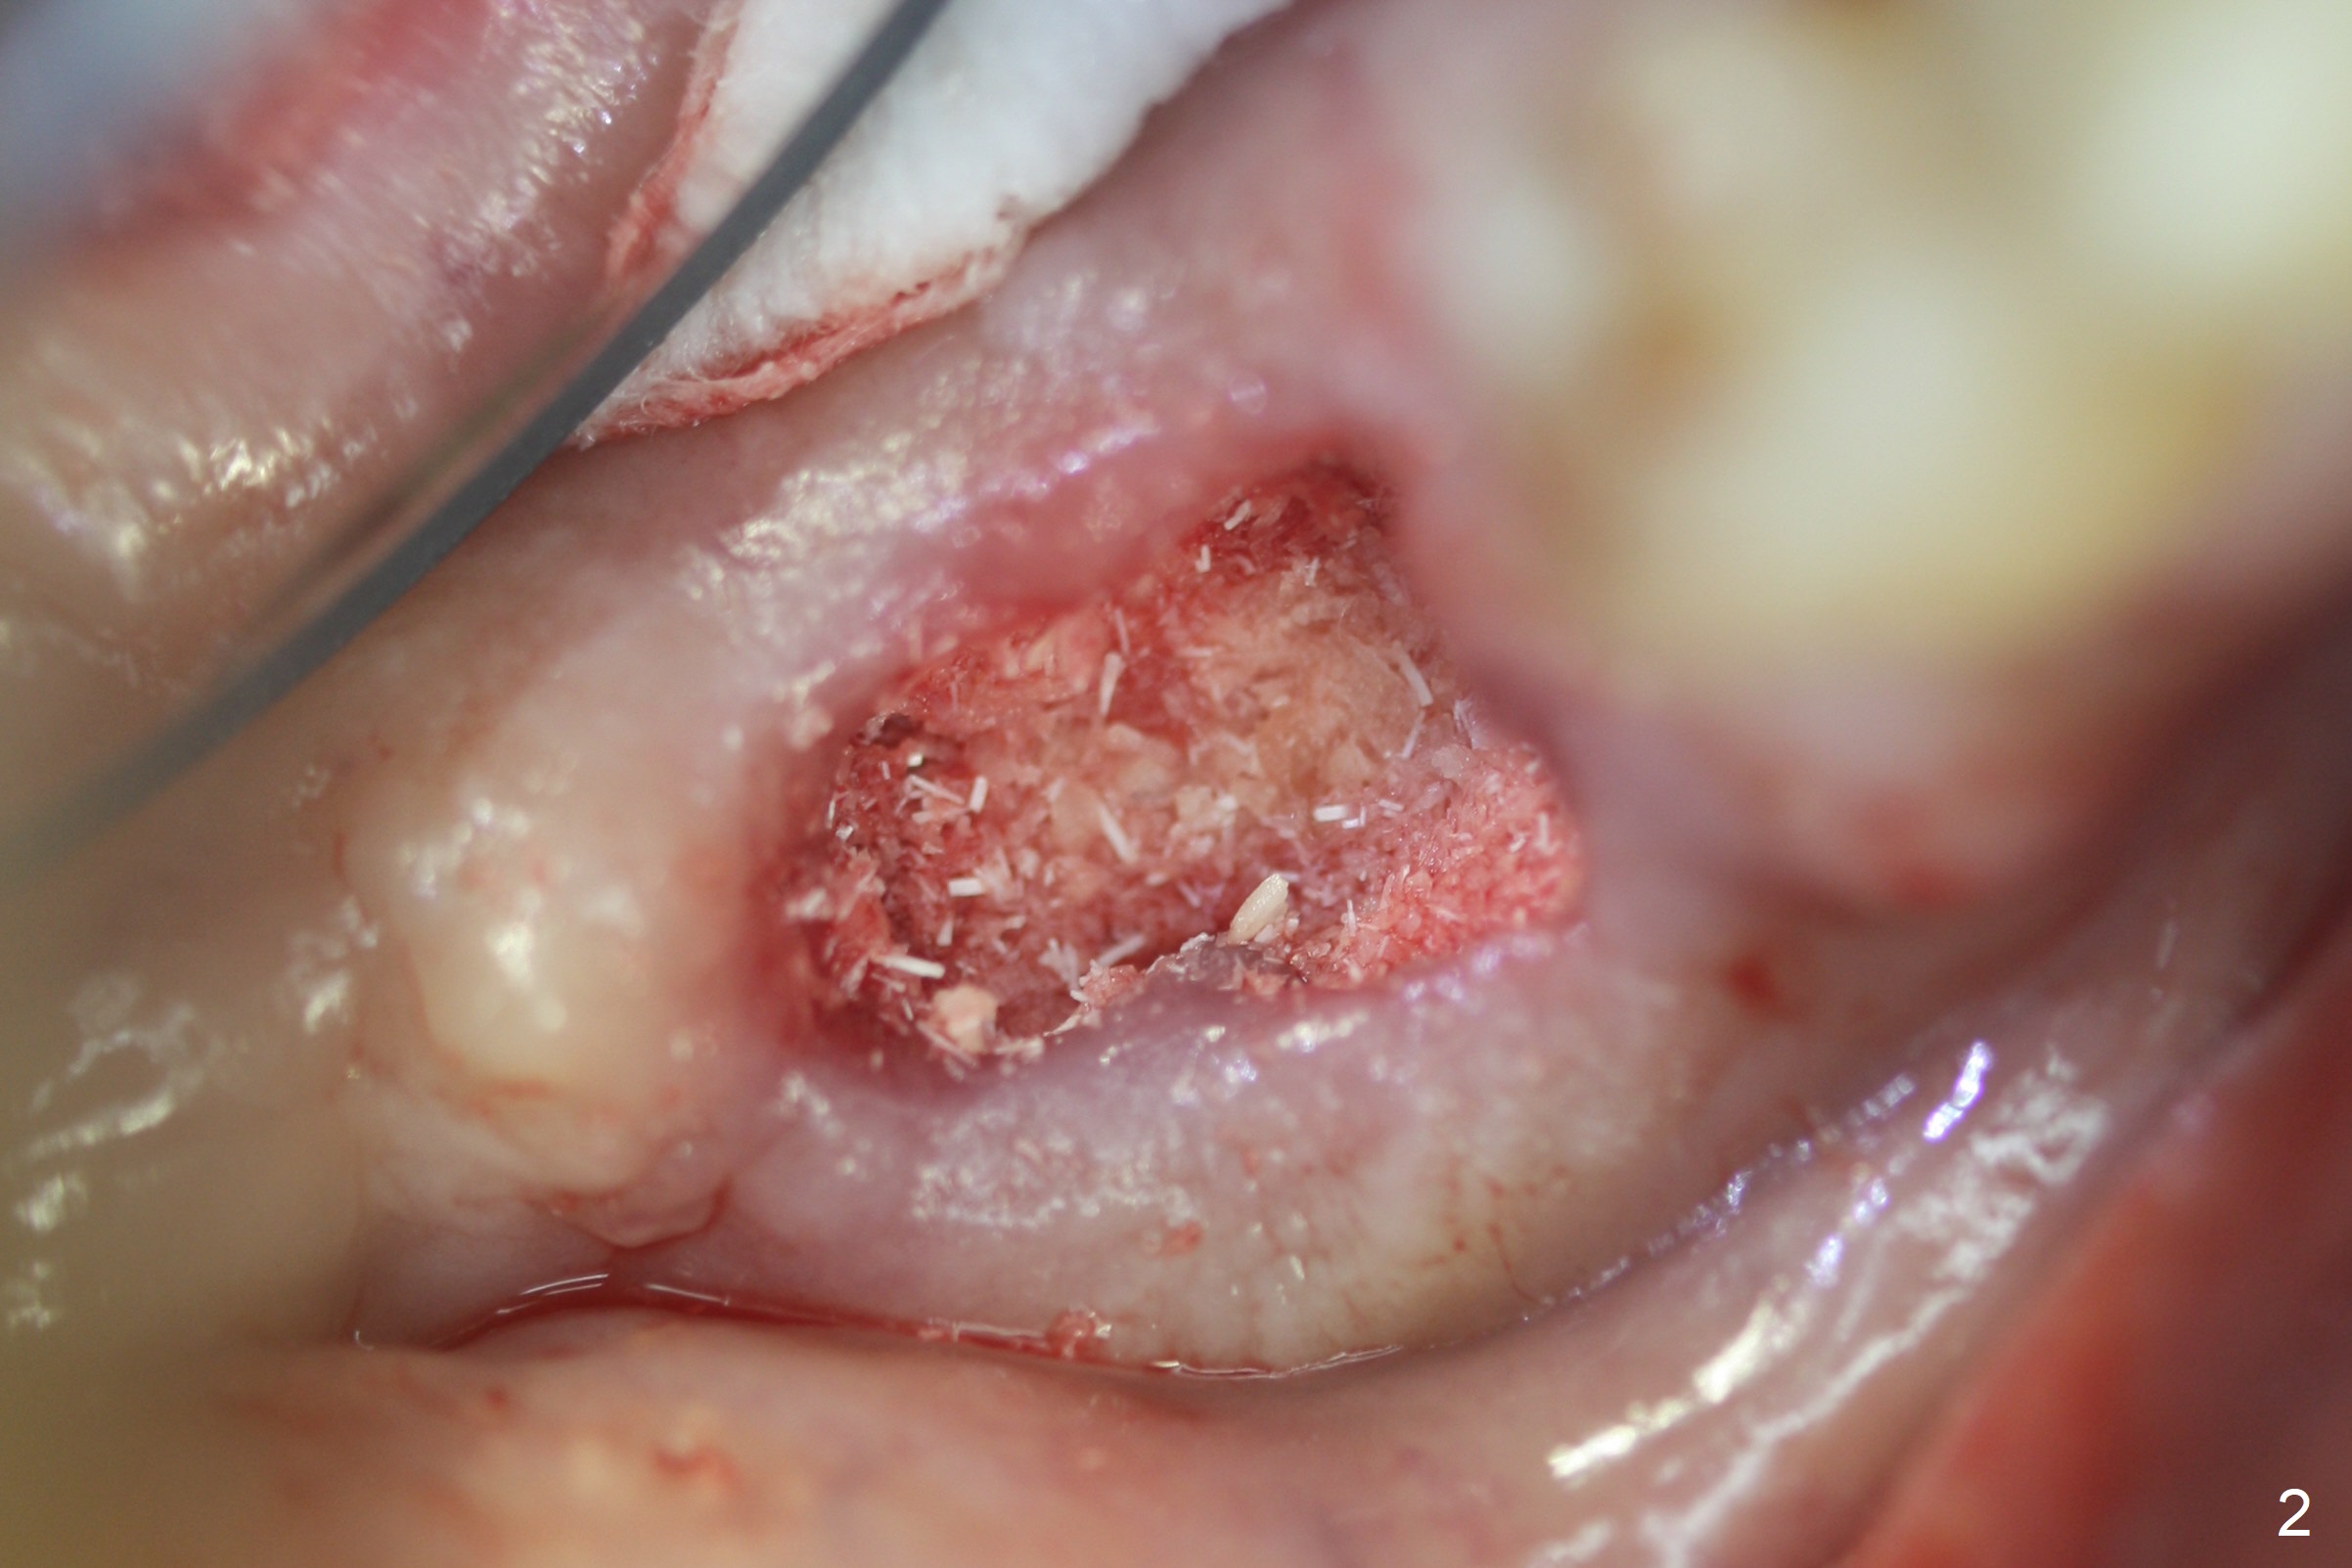

Extraction of the mobile tooth #31 (Fig.1) and debridement of the large socket are not difficult. But making osteotomy buccally does not seem to be easy. It will be difficult to restore. Instead, socket preservation is accomplished by filling the socket with approximately 1.5 cc of Mineralized Cortical/Cancellous allograft until the crest (Fig.2,5). The socket opening is closed by insertion of 4 pieces of PRF membranes (Fig.3) and 4-0 Chromic gut sutures (Fig.4). In the end of surgery, it appears that osteotomy in the center of the socket could be a better approach. Postop re-analysis of CT (Fig.6) and PA (Fig.7) shows that there is 3.9 mm of the native bone to support a 5.5x10 mm implant. Sinus Lift Master Kit should be used with 2 mm initial drill and 2.8 and 3.6 mm round drills with 4 mm stopper.